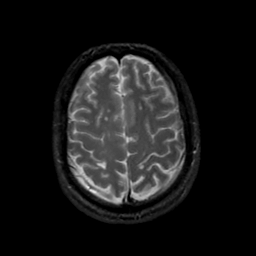

MR Study #19, August 25, 1991 -- Slice #39

[Home][Help][Clinical][Tour 1][Tour 2] Slice 39